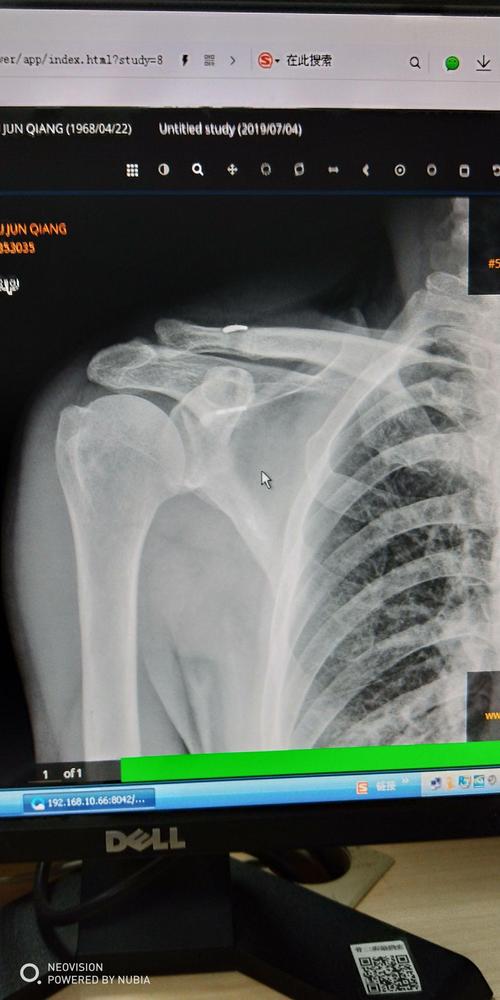

肩锁关节脱位分度,肩锁关节图片

肩锁关节脱位

右肩锁关节脱位纽扣钢板固定

求助,各位老师看看是否肩锁关节脱位?

肩锁关节脱位 该如何治疗? 需要手术吗?

肩锁关节脱位图片

肩锁关节脱位三度图片

右肩锁关节脱位图片

肩锁关节脱位x线图片

肩锁关节脱位图片表现